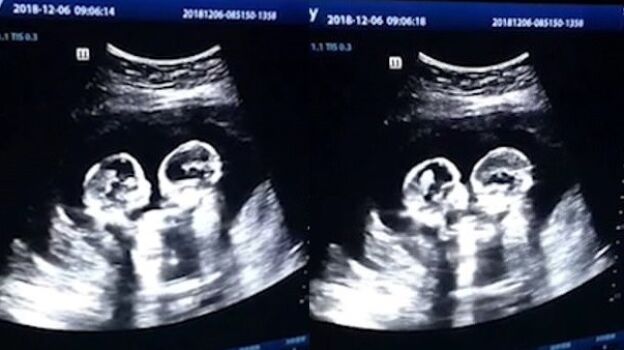

COMPARTÍAN EL MISMO SACO AMNIÓTICO

Una ecografía capta a dos gemelas 'peleandose' dentro del útero de su madre

Las hermanas, que han nacido sanas y salvas, se 'golpeaban' durante las revisiones ginecológicas de su madre.

En Yinchuan, China, dos gemelas fueron grabadas el pasado diciembre 'peleándose' dentro del útero durante una revisión en el cuarto mes de gestación, según ha recogido el 'China Daily'.

La ecografía reveló cómo las dos hermanas comenzaban a darse 'patadas' y 'golpes' en el interior de la barriga de su madre.

Las gemelascompartían el mismo saco amniótico (gemelos monoamnióticos) por lo que el embarazo era raro y además de alto riesgo. No obstante tenían un 50% de posibilidades después de las 26 semanas y así lo han hecho.